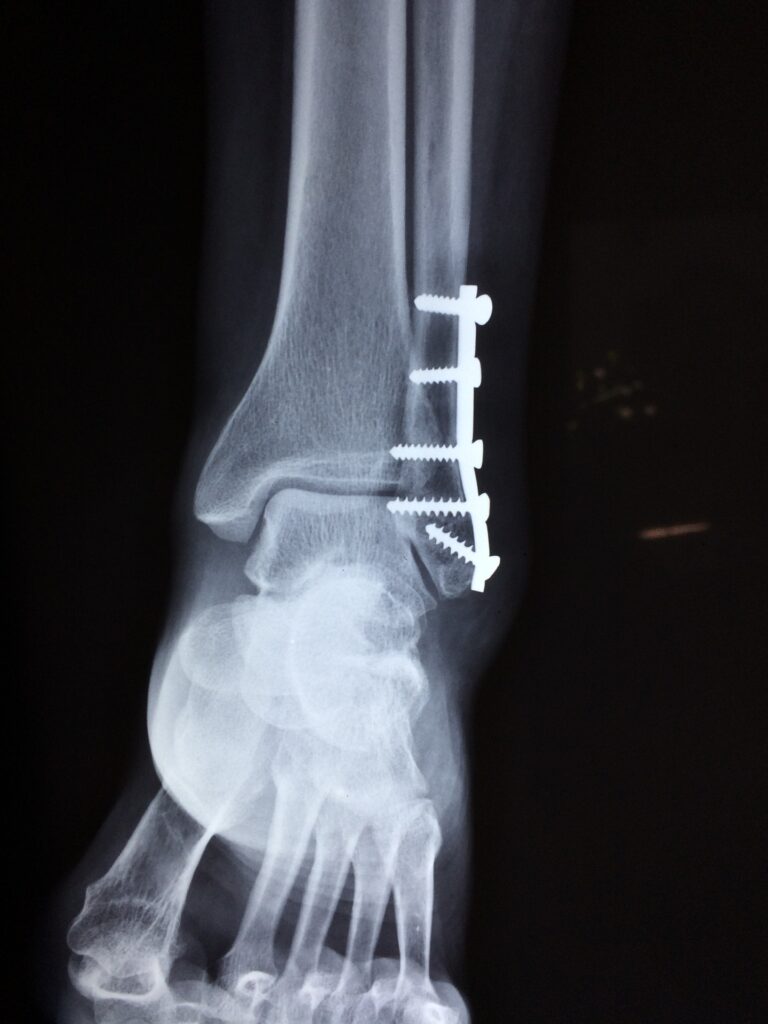

- Fractures, Bone injuries, Ligament injuries, Muscle injuries, Muscle pain, Sprains

- Fracture fixing surgeries, Joint replacement